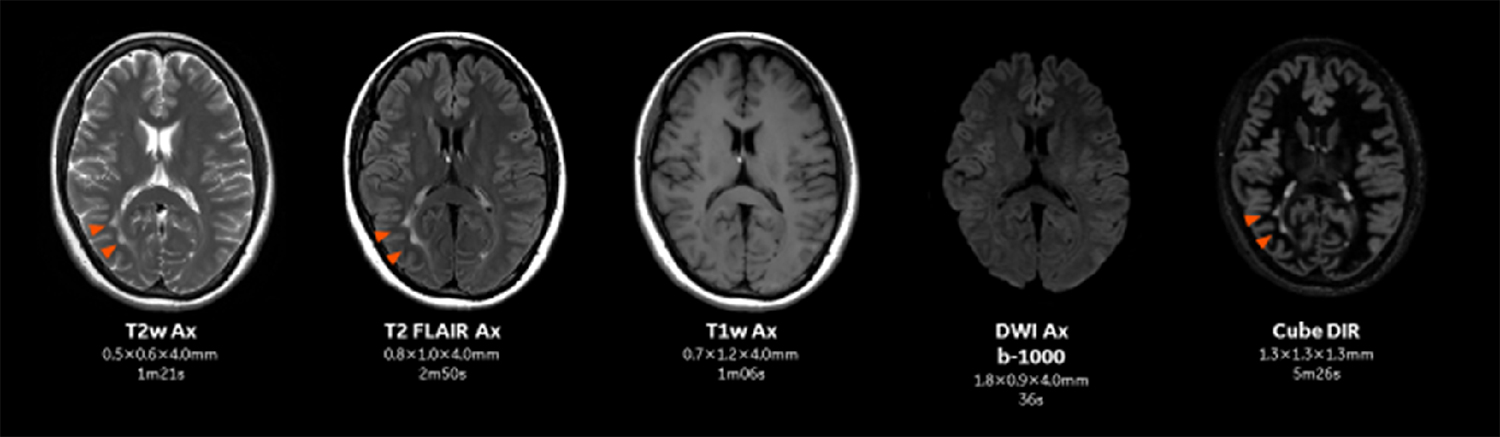

2-1. 脳脊椎領域

従来の頭部MRのプロトコルでは全脳を5mmで行っていたが、AIR™ IQ Editionの導入によりスライス厚を3-4mmに変更した。従来のプロトコルより薄いスライスで撮像することにより、部分容積効果が軽減する。

今までMRIの診断ではCTとは異なり部分容積効果を無意識に許容していたが、Thin slice化によって想定以上の診断能向上効果を感じている。またThin slice化により全脳をカバーするのにスライス数が増加しているが、加算回数を減らしたり、パラレルイメージングのファクターを上げたりすることによって従来のプロトコルより短時間で撮像を行うことが可能となっている(Figure.1)。

Pironeer_Kosugi_03.jpgFigure.1

SIGNA Pioneer 3.0T AIR IQ Editionにおける頭部MR検査のプロトコル。従来より薄いスライスで短時間に撮像が可能となっている。